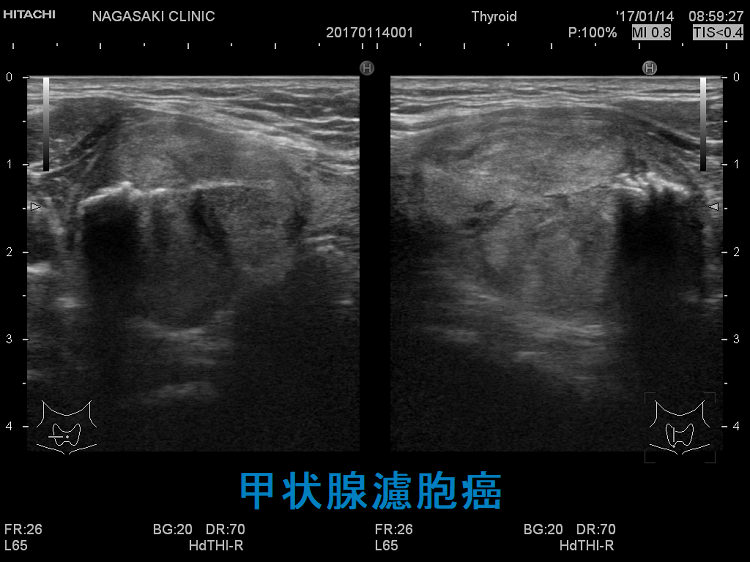

微小浸潤型濾胞癌でも巨大なものは、血管浸潤・遠隔転移します。写真のケースは 4cm以上の微小浸潤型濾胞癌で、切除標本にて血管浸潤を4カ所以上認め、Ki-67 labeling index 7% 高値(>5%)だった(エコーでは内部血流が少なかったのに)。